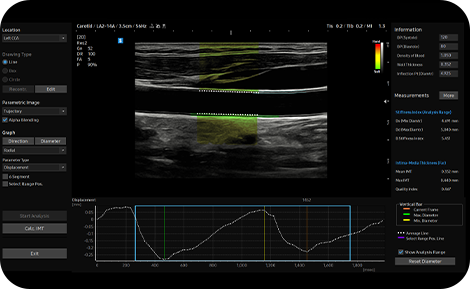

Detect functional changes of

cardiovascular vessels

ArterialAnalysis™ detects functional changes of vessels, providing measurement values such as the stiffness, intima-media thickness and pulse wave velocity of the common carotid artery.

medical solution : ArterialAnalysis™

Measure IMT in one click

AutoIMT+ is a screening tool to analyze a patient’s potential risk of cardiovascular disease. It allows easy intima-media thickness measurement of both the anterior and posterior wall of the common carotid by the click of a button.

cardiovascular ultrasound tech : AutoIMT+